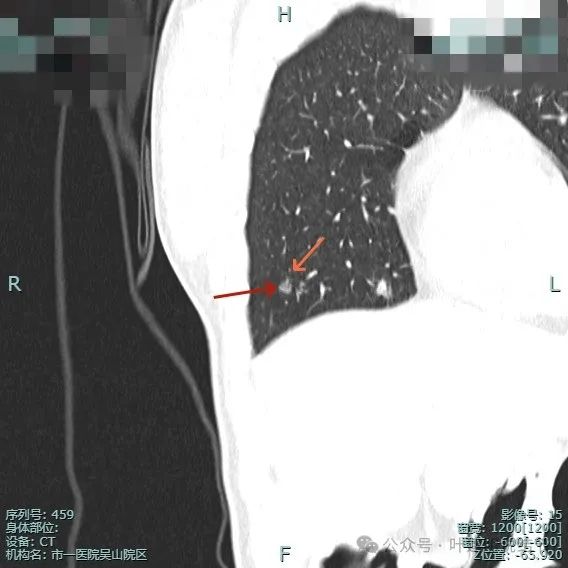

左侧病灶10:

病灶表面不平有分叶与凹凸,密度也不均匀,有点状实性成分,邻近胸膜(叶间裂)。

表面有毛刺,灶内有小空泡征,边缘毛糙不平,密度显得不均匀。

部分边缘有毛刺或小棘突,病灶边上有扩张的细支气管,整体内部密度欠均匀。

边缘毛糙,血管进入,灶内密度显得杂乱。

有扭曲的血管进入血管,表面有凹陷与分叶。

密度不太纯,表面不平,血管有异常增粗。

胸膜有轻微牵拉,表面不平,多处微小血管进入,整体密度显得不匀。

血管征明显、灶内小空泡征、胸膜牵拉、边缘细毛刺征。

整体看上去密度不均、边缘不平、灶内空泡征以及细毛刺征均明显。